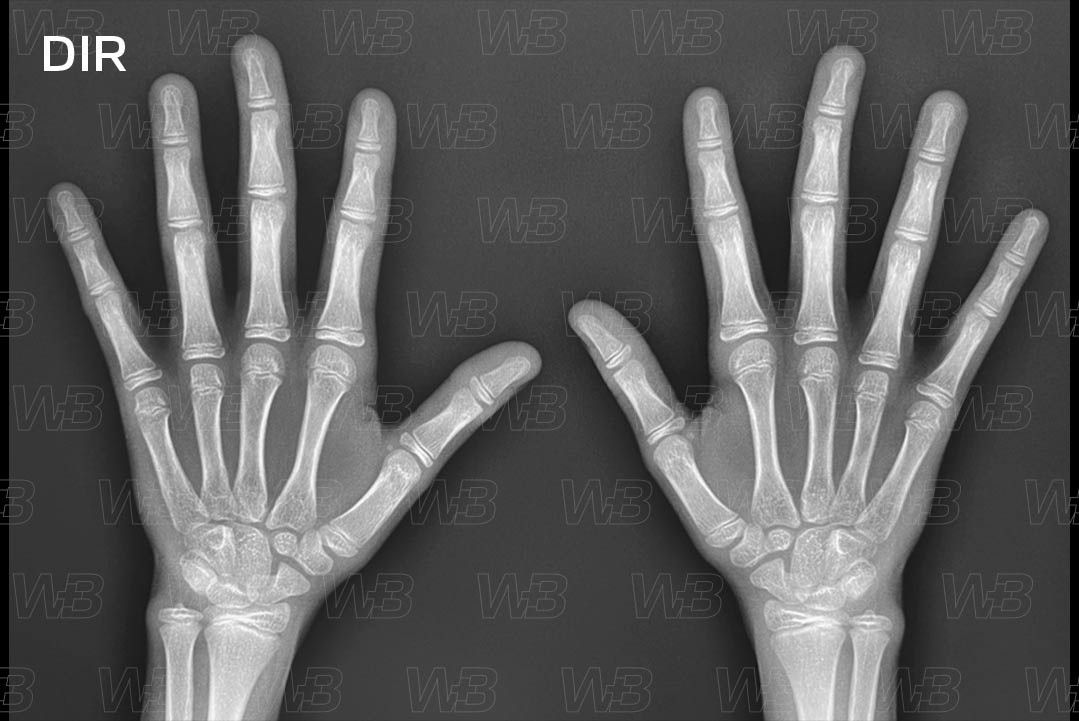

RADIOGRAFIA MÃOS E PUNHOS (IDADE ÓSSEA) [cms-watermark]

Feminino

12 anos:

• Estiloide ulnar bem proeminente;

• Epífise do rádio capeia a metáfise.